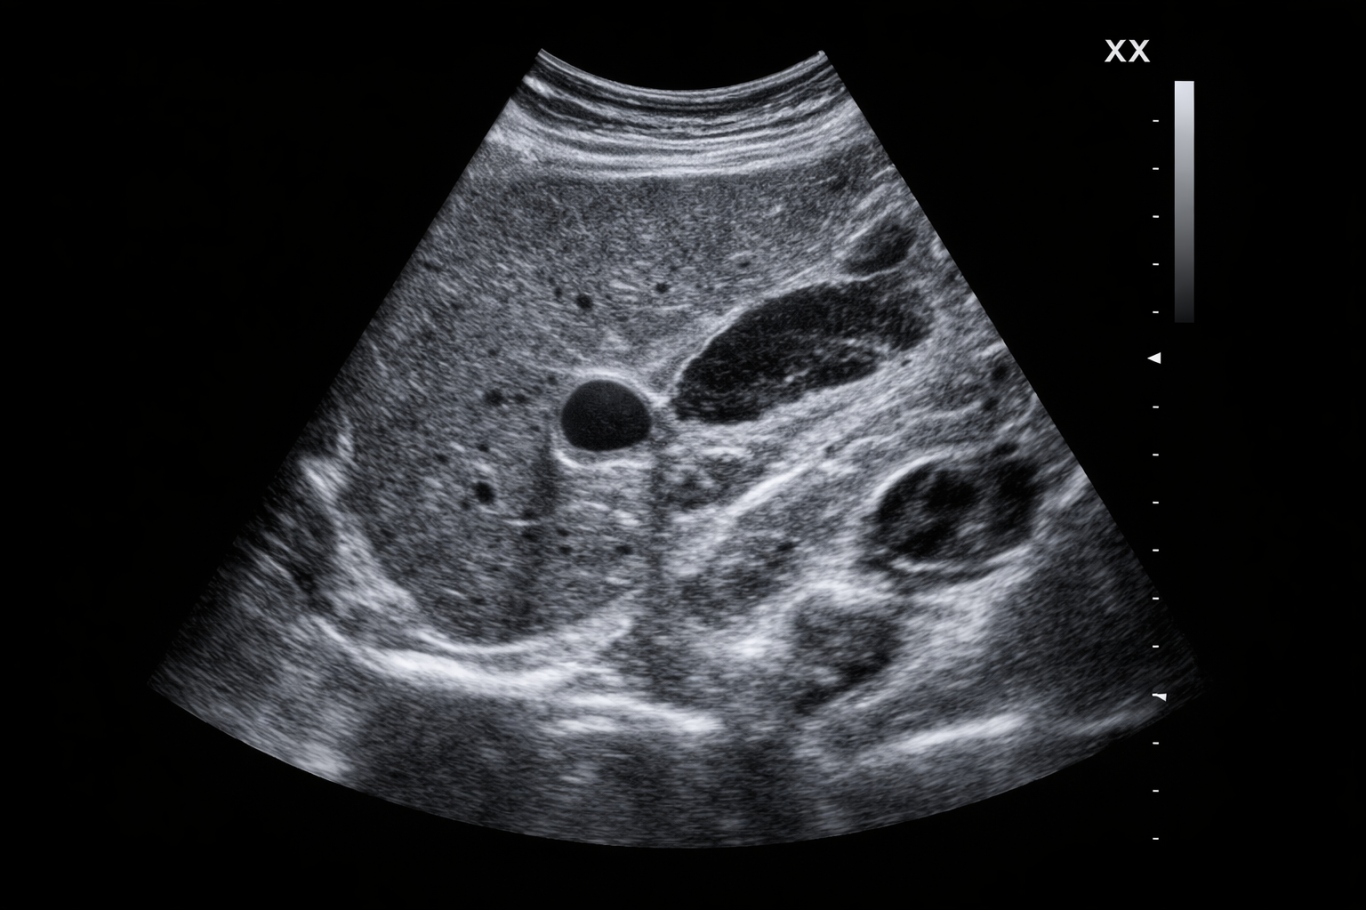

Echographie

L’échographie est un examen d’imagerie médicale qui utilise des ultrasons pour visualiser en temps réel les organes, les tissus et les vaisseaux du corps. Elle est indolore et ne comporte aucune irradiation. Cet examen est largement utilisé pour explorer de nombreuses régions du corps, notamment l’abdomen, les muscles, les articulations et certains organes superficiels.